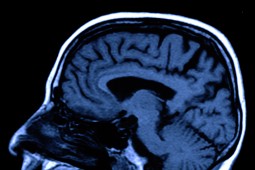

A brain MRI. MRI (Magnetic Resonance Imaging) is one of the many technologies made possible as a result of physics research.

In "From a Physicist's Mind", Heidi Schellman writes an equally down-to-Earth story summarizing how the superconducting magnets work at Fermilab's Tevatron particle accelerator. She also explains how the need for cutting-edge tools for experiments has jump started technological advances leading to better products and services used in everyday life, including MRI machines, superconducting wire and the World Wide Web.